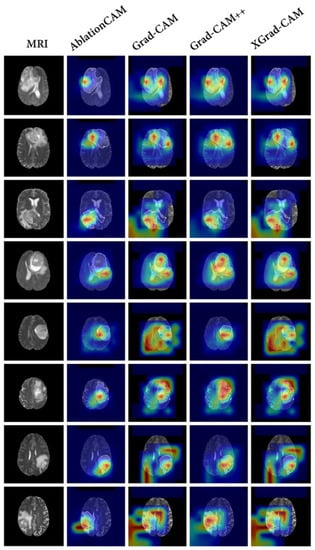

4.7. Comparison with Baseline Visualization Methods

To compare our proposed interpretable method with conventional methods, we conducted a comparison using the baseline model SEResNet, which exhibited the best classification performance. We selected AblationCAM [35], Grad-CAM [21], Grad-CAM++ [36], and XGrad-CAM [37] as the baseline visualization methods to explain the model’s decision-making process. The results are shown in Figure 6.

In general, the results of the baseline models exhibited a diffuse distribution pattern. Among all of the baseline methods, AblationCAM [35] performed the best and was able to focus on the tumor region more accurately. However, it still exhibited some false attention, such as focusing on the black background. This false attention is often problematic in interpretation methods, since the model does not utilize any information from the black background that would be beneficial for classification.

Figure 6. The results of baseline visualization methods. In the traditional methods, AblationCAM [35], Grad-CAM [21], Grad-CAM++ [36], and XGrad-CAM [37] are used to explain the trained SEResNet [29]. Specifically, The first column shows the T2 fluid attenuated inversion recovery (FLAIR) MRI. Columns 2–5 show the visual explanations for AblationCAM [35], Grad-CAM [21], Grad-CAM++ [36], and XGrad-CAM [37], respectively. Different colors in a heatmap represent varying levels of attention. In these examples, the transition from red to blue indicates a descending order of attention.